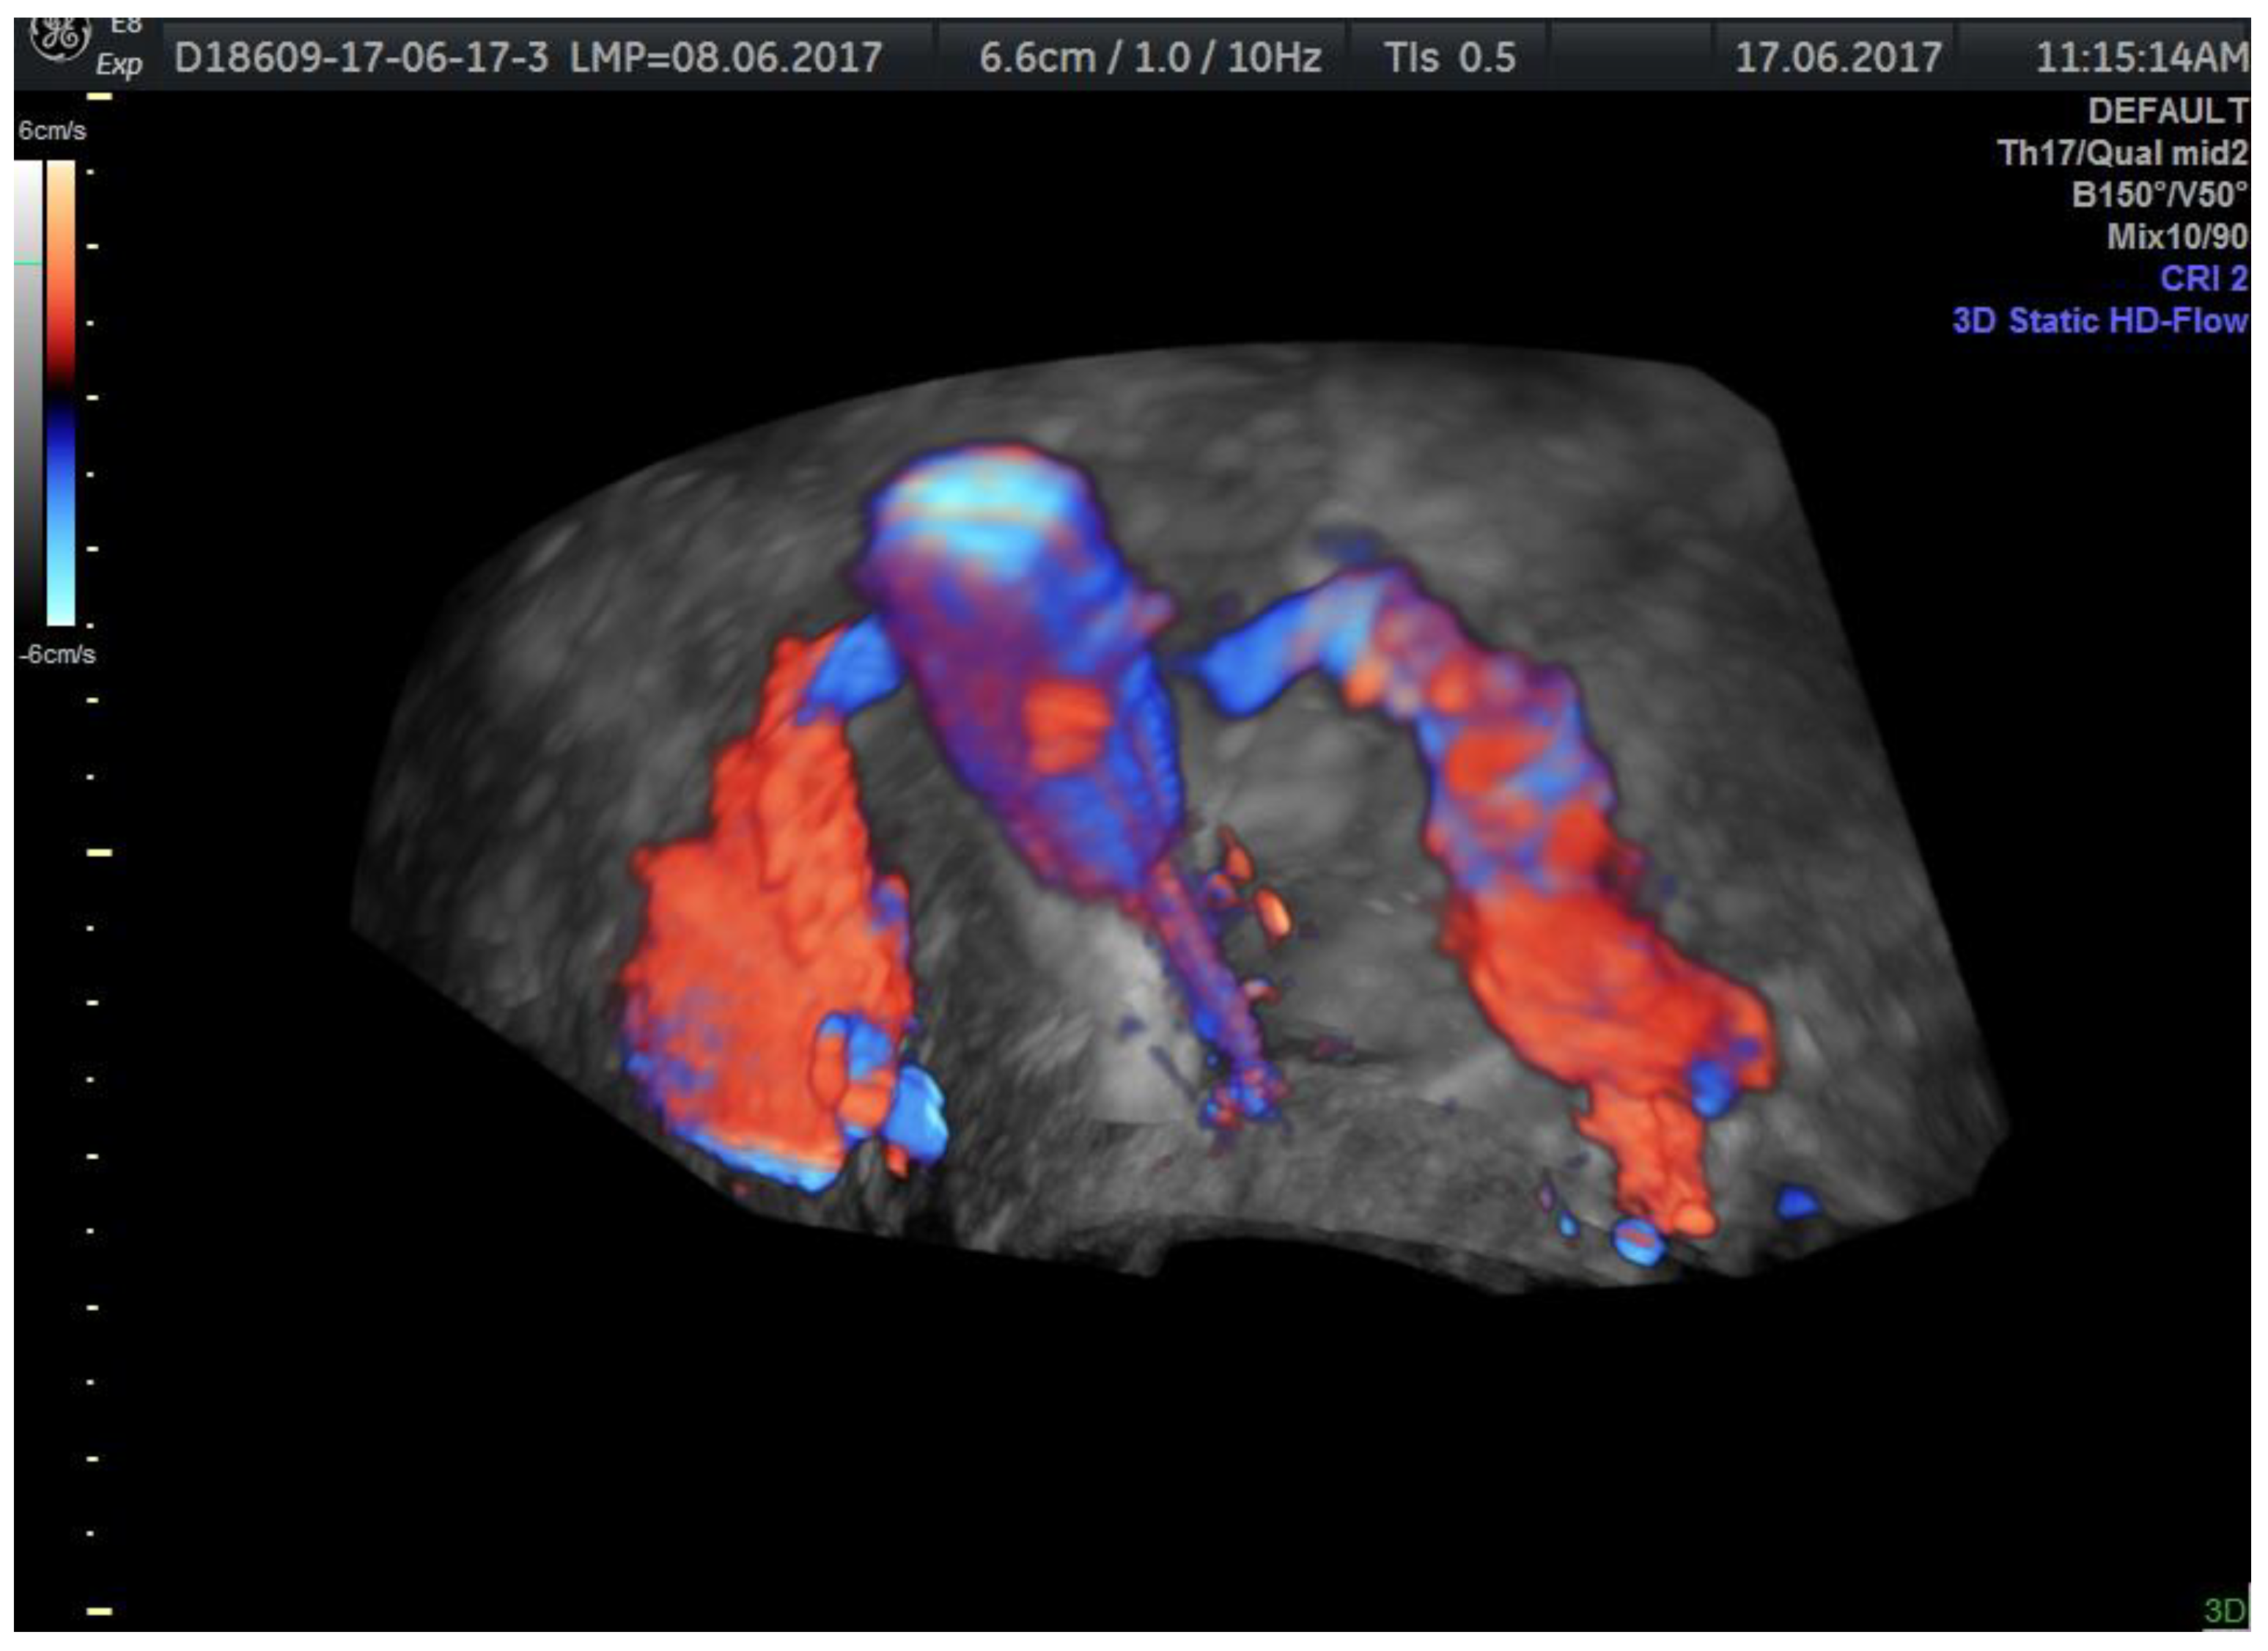

| Tubal patency evaluation requires evaluating the entire substance passage through the tubes | Visualizing the contrast substance progression through the entire tubal pathway, its evacuation near the ovary, and finding the contrast substance at the end of the procedure in the pouch of Douglas or as a fine hyperechoic line near the uterus | Thin line of contrast substance visualized from the interstitial to the infundibular part of the fallopian tube and contrast substance present in the cul-de-sac are signs of tubal patency [31] |

| The use of 2D sepia mode | The functional dynamics of the tubes are optimally evaluated; Using 3D mode on HG-Flow offers spectacular images without acquiring a real informational benefit | 3D-HyFoSy, with or without Doppler techniques, does not bring additional information compared to 2D-HyFoSy when used by a ultrasonographer who has knowledge of the pelvic anatomy [29] |